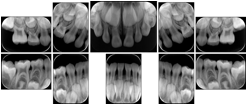

2. A patient requests cosmetic surgery to enhance their facial appearance. The case requires consultation between an orthodontist in New York and an oral surgeon in California. The cephalometric series of 2D projections constructed from a volumetric CT data set that is used for the discussion is arranged by a Structured Display for transfer between the two practitioners.

Cephalometric Series Structured Display

Figure OO-2. Cephalometric Series Structured Display